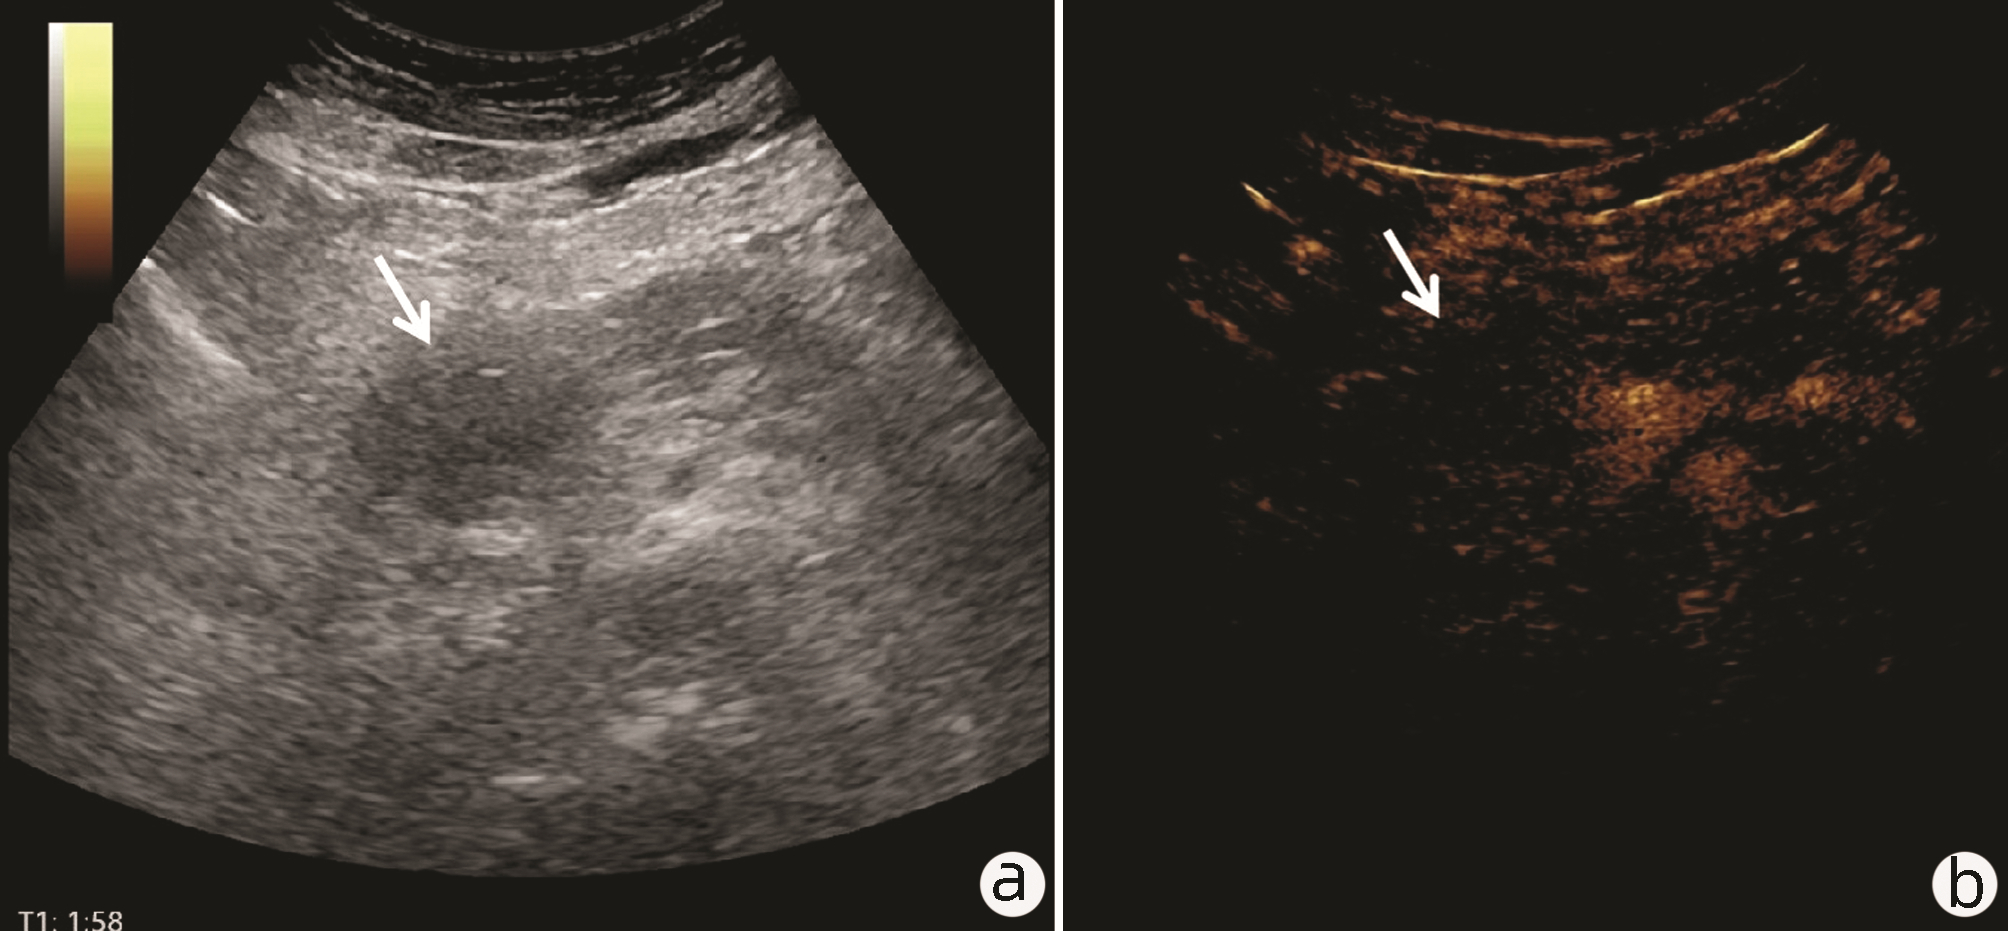

Value of 18F-FDG PET/CT, contrast-enhanced ultrasound, and their combined use in differential diagnosis of benign and malignant pancreatic lesions: A comparative study

Lichun ZHENG, Xiaoming ZHANG, Tianying YU, Jie LI, Xiaoqian DENG, Xiangliu OUYANG

2022, 38(12): 2774-2779. DOI: 10.3969/j.issn.1001-5256.2022.12.017

Abstract(2246) HTML (1599) PDF (3391KB)(53)

Abstract:

Objective  To assess the value of 18F-FDG PET/CT, contrast-enhanced ultrasound, and their combination in the differential diagnosis of benign and malignant pancreatic lesions.  Methods  A retrospective analysis was performed on patients with pancreatic lesions who underwent18F-FDG PET/CT and contrast-enhanced ultrasound who were admitted to Tangshan Gongren Hospital from January 2015 to December 2020. The imaging results were confirmed by pathology examination to evaluate diagnostic sensitivity, specificity, accuracy, positive and negative predictive value. The t-test was used for comparison of continuous data between two groups, and the chi-square test was used for comparison of categorical data between groups.  Results  There were 83 malignant lesions and 25 benign lesions in 108 patients. The sensitivity, specificity, accuracy, positive and negative predictive value were 86.75%, 80.00%, 85.19%, 93.51% and 64.52% for 18F-FDG PET/CT; and 69.88%, 76.00%, 71.30%, 90.63% and 43.18% for contrast-enhanced ultrasound, respectively. The two methods differed significantly in sensitivity and accuracy (all P < 0.05), but not in specificity, negative and positive predictive value (all P > 0.05). When combined with the contrast-enhanced ultrasound, 18F-FDG PET/CT had an increased sensitivity, specificity, accuracy, positive and negative predictive value of 90.36%, 84.00%, 88.89%, 94.94% and 72.41%, respectively, though this was not statistically significant due to the increased signal of blood supply in the lesions.  Conclusion  18F-FDG PET/CT has a better performance than contrast-enhanced ultrasound in the differential diagnosis of benign and malignant pancreatic lesions, and their combination can improve the diagnostic value.